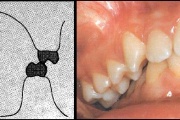

Esimese jäävmolaari ektoopiline lõikumine

) Röntgenülesvõte. Ülemise esimese jäävmolaari lõikumine on takistatud 2. piimamolaari tõttu

Ravijärgne seis. Jäävhammas on täielikult lõikunud.